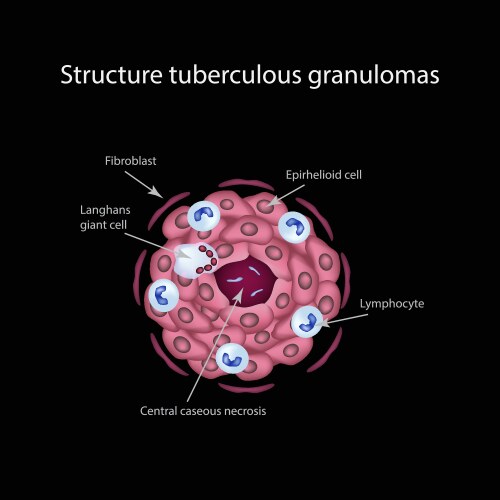

- Structure